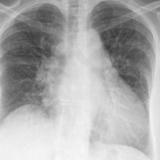

CHF progression

Date: 11/05/2005

Views: 3430